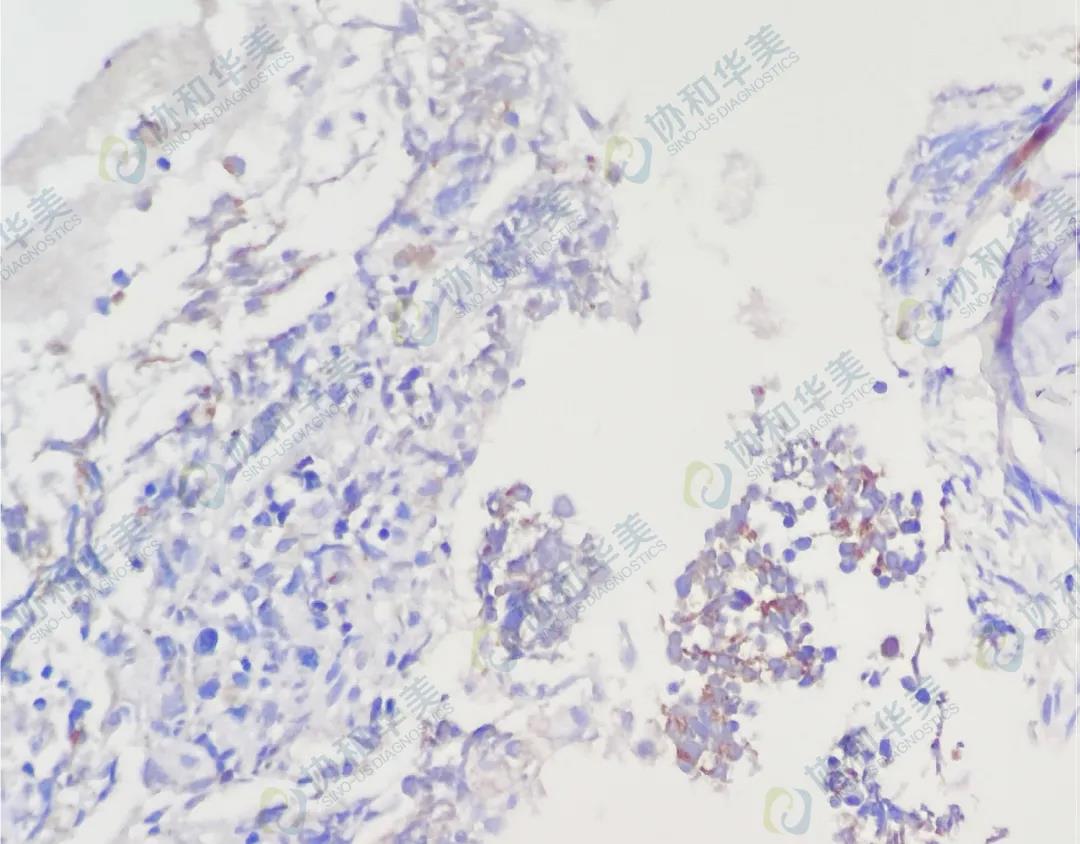

MPO染色

MPO染色阴性

CK